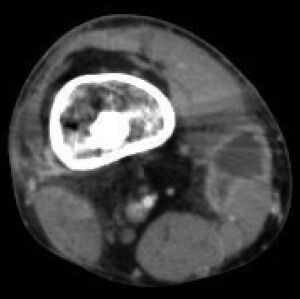

| Osteomyelitis of the 1st toe | |

Radiographs and CT are the initial method of diagnosis, but are not sensitive and only moderately specific for the diagnosis. They can show the cortical destruction of advanced osteomyelitis, but can miss nascent or indolent diagnoses.[23]

Confirmation is most often by MRI.[24] The presence of edema, diagnosed as increased signal on T2 sequences, is sensitive, but not specific, as edema can occur in reaction to adjacent cellulitis. Confirmation of bony marrow and cortical destruction by viewing the T1 sequences significantly increases specificity. The administration of intravenous gadolinium-based contrast enhances specificity further. In certain situations, such as severe Charcot arthropathy, diagnosis with MRI is still difficult.[23] Similarly, it is limited in distinguishing avascular necrosis from osteomyelitis in sickle cell anemia.[25]

Diagnosis of osteomyelitis is often based on radiologic results showing a lytic center with a ring of sclerosis.[13] Culture of material taken from a bone biopsy is needed to identify the specific pathogen;[27] alternative sampling methods such as needle puncture or surface swabs are easier to perform, but cannot be trusted to produce reliable results.[28][29]